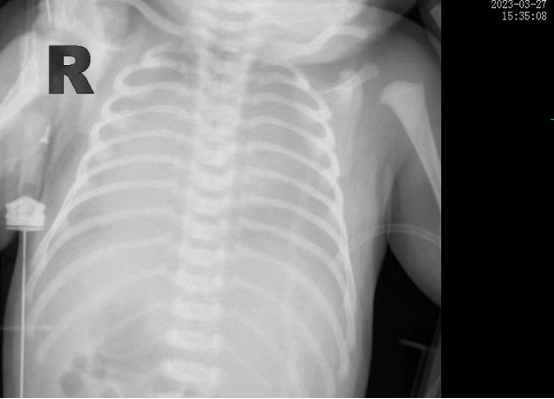

時間追溯到3月27日,該患兒出生時哭聲欠連貫,全身可見黃色胎糞附著,羊水三度污染,呼吸稍促,血氧飽和度低,立即轉入新生兒科。醫(yī)生立即予以清理呼吸道,常壓給氧,建立靜脈通道后抱入暖箱復溫,同時以無創(chuàng)輔助通氣。然而患兒呼吸窘迫癥狀正在進行性加重,胸片提示“白肺”,結合血氣分析等檢查后,患兒被診斷為“急性呼吸窘迫綜合癥”、“呼吸衰竭”。時間就是生命,主管醫(yī)生張海嬌在與家屬充分溝通同時,副主任醫(yī)師鐘玉芬立即帶領新生兒醫(yī)護團隊快速采取急救措施,給予患兒氣管插管術進行有創(chuàng)呼吸機高頻震蕩通氣,并從氣管內(nèi)滴入PS(肺表面活性物質(zhì)),以降低肺泡表面張力,增加肺順應性,患兒血氧這才穩(wěn)定下來。

在科室團隊的共同努力下,患兒歷經(jīng)5天有創(chuàng)通氣5天無創(chuàng)通氣,再調(diào)整為5天吸氧后已經(jīng)實現(xiàn)呼吸自由,復查肺部CT,終于看到白肺已云開霧散。4月15日,歷時17天的醫(yī)療救治,患兒順利出院,回到了媽媽的懷抱。

據(jù)悉,新生兒急性呼吸窘迫綜合征(ARDS)是一種嚴重威脅新生兒生命的呼吸危重癥,其主要臨床表現(xiàn)為不同程度的低氧血癥,雙肺彌漫性透光度下降,炎性滲出伴肺順應性下降。根據(jù)國際新生兒ARDS多中心研究中期報告,新生兒ARDS病死率大約為20%,而早期識別,進行良好的肺復張,預防及治療肺動脈高壓、心臟衰竭、液體管理及積極抗感染等綜合治療以降低病死率。